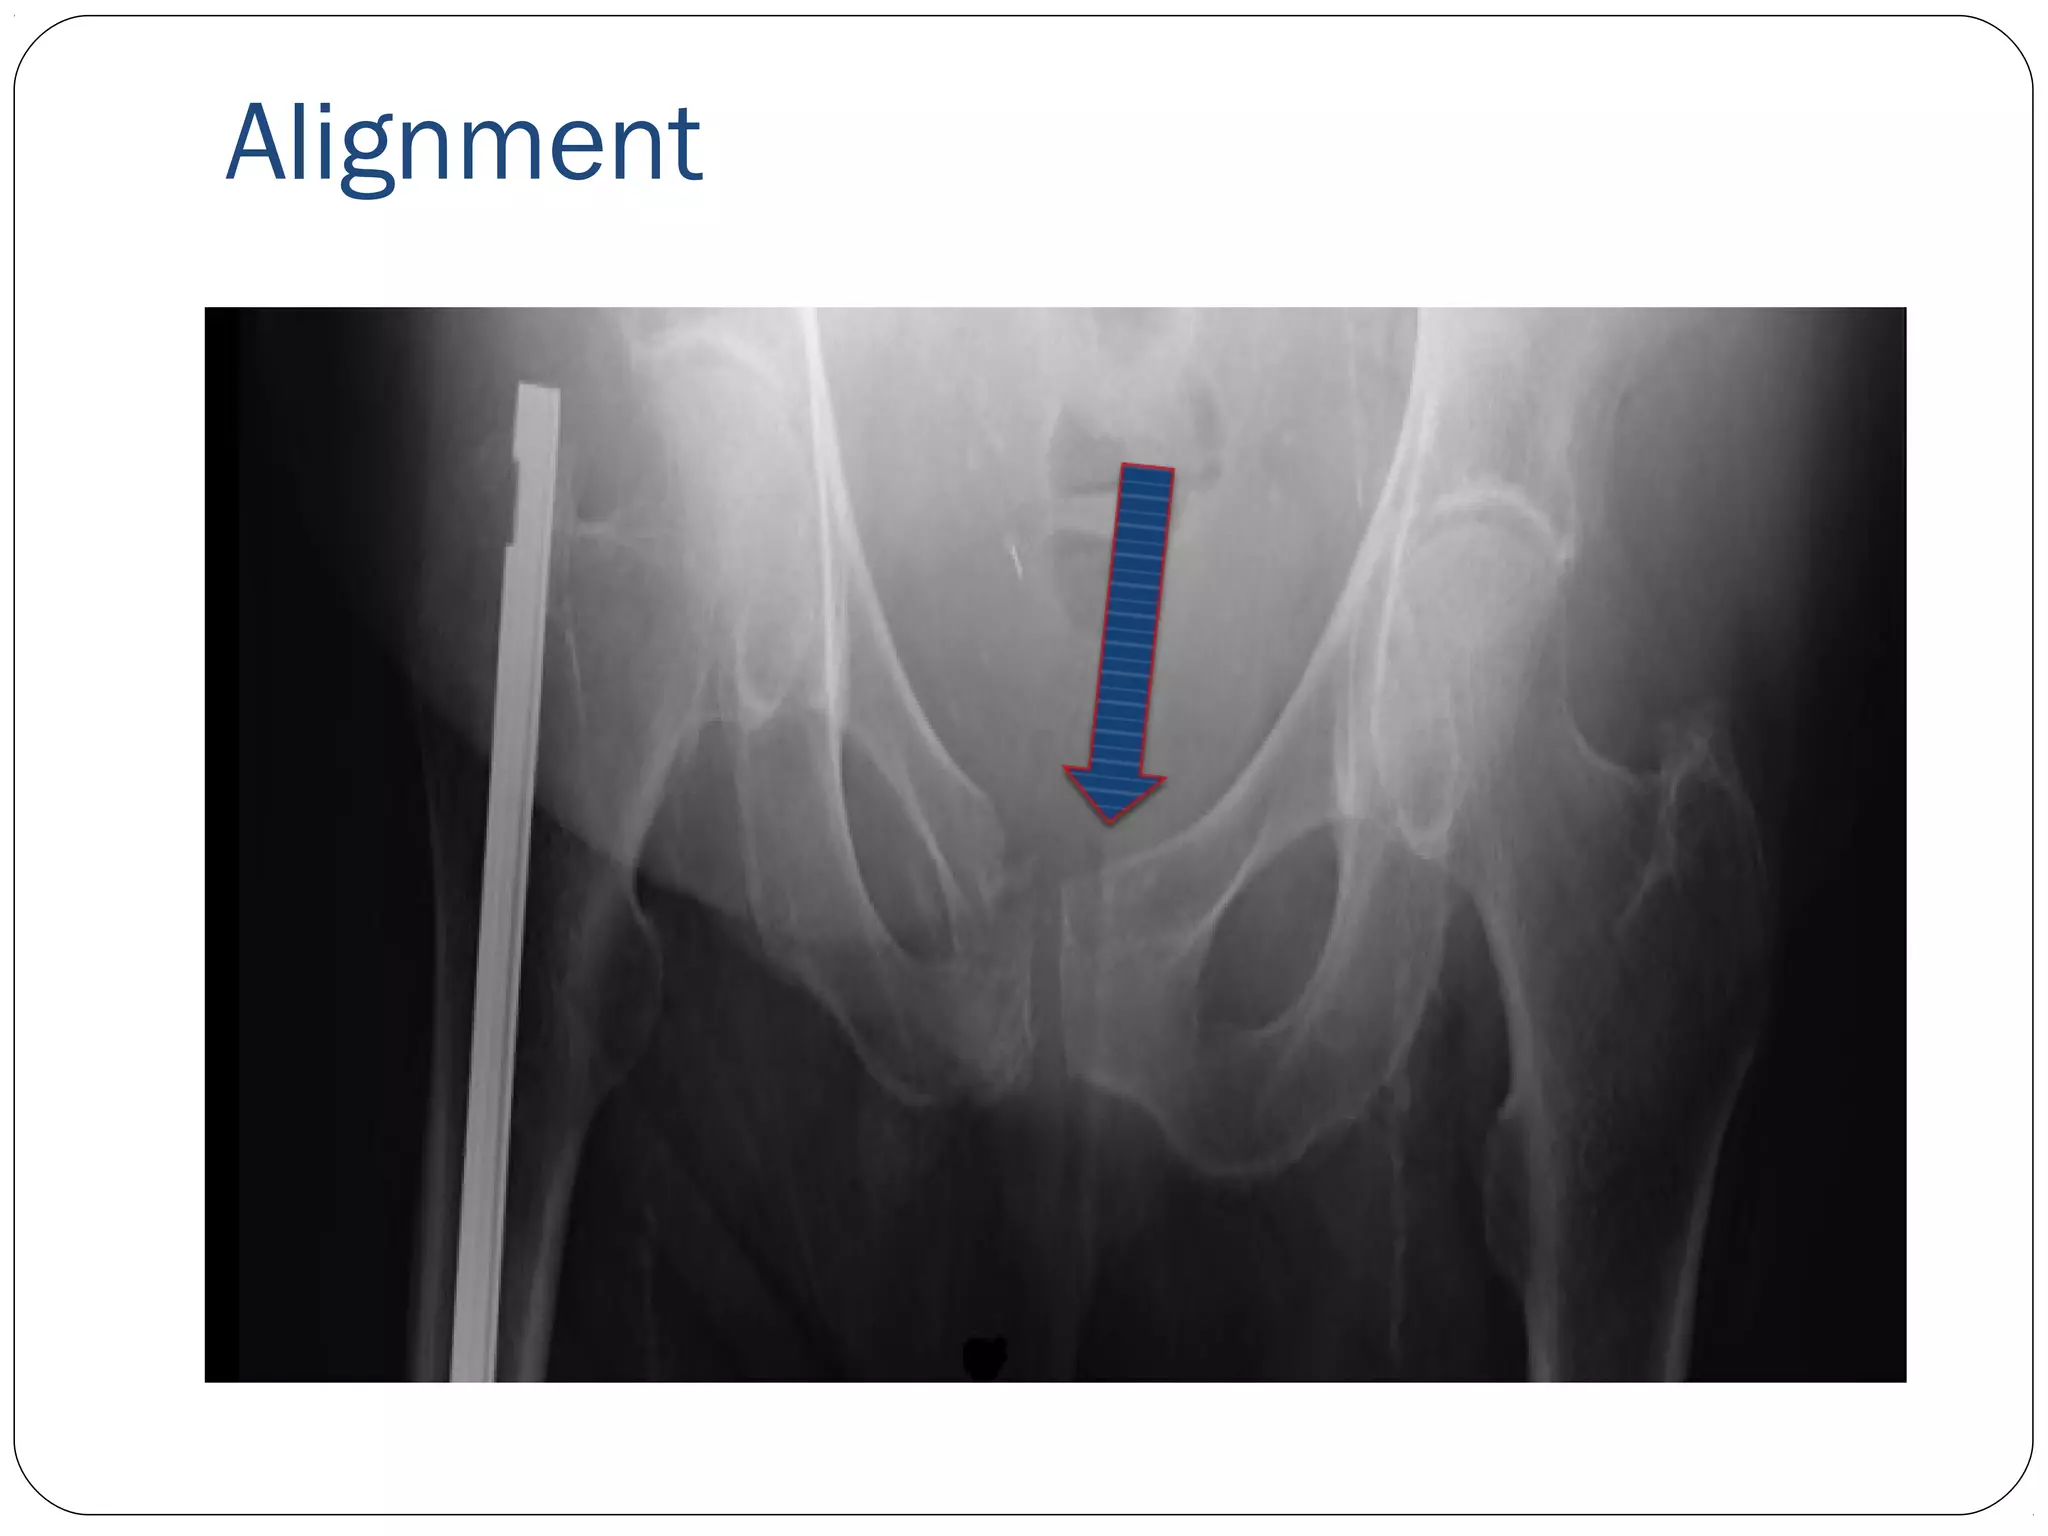

A-B-C-D

A- Alignment- is the bone in good general

Alignment